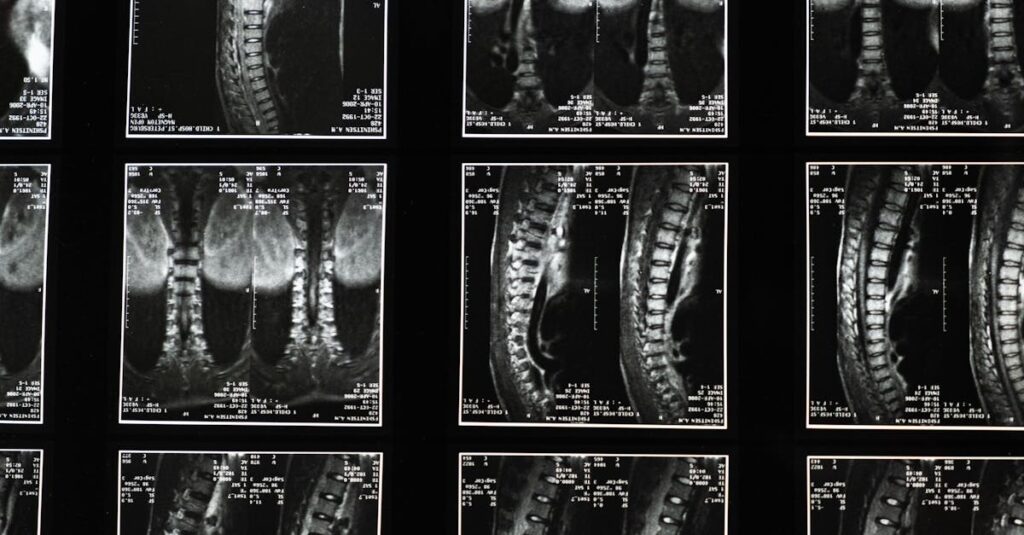

Quels examens permettent de diagnostiquer la sciatique?

Une IRM ou une radiographie est généralement nécessaire pour confirmer la cause de la sciatique.